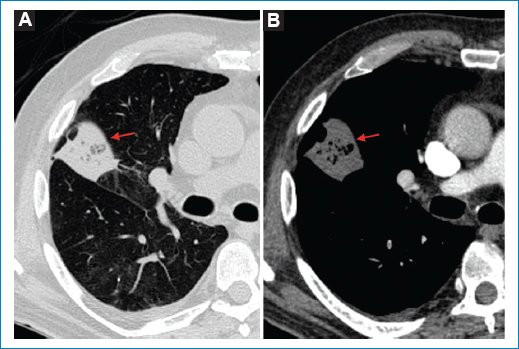

- Opacidad periférica con radiolucencia central: con una especificidad del 98% y sensibilidad del 46%, es el signo más específico para IP5. Consiste en una opacidad consolidativa periférica que contiene áreas de radiolucencia central. Dicho hallazgo se debe principalmente al llenado alveolar con contenido hemático, que se traduce en áreas de vidrio esmerilado central. También es considerada secundaria a necrosis central, con una reacción inflamatoria alrededor, opacidad consolidativa periférica, donde las zonas más excéntricas pueden representar un tejido viable (Fig. 1)6.